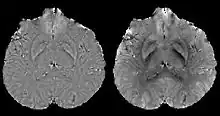

COSMOS assumes a model-free susceptibility distribution and keeps full fidelity to the measured data. This method has been validated extensively in in vitro, ex vivo and phantom experiments. Quantitative susceptibility maps obtained from in vivo human brain imaging also showed high degree of agreement with previous knowledge about brain anatomy. Three orientations are generally required for COSMOS, limiting the practicality for clinical applications. However, it may serve as a reference standard when available for calibrating other techniques.

MEDI has also been validated extensively in phantom, in vitro and ex vivo experiments. In an in vivo human brain, MEDI calculated QSM showed similar results compared to COSMOS without statistically significant difference.[15] MEDI only requires a single angle acquisition, so it is a more practical solution to QSM.